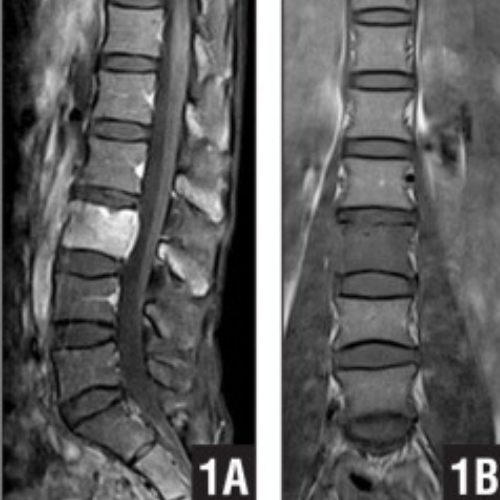

Tanı aşamasında en güçlü araç kontrastlı MR (Emar) görüntülemesidir. Kemik yapının detaylı incelenmesi için Bilgisayarlı Tomografi (BT) ve tümörün yayılımını belirlemek için PET/CT gibi yöntemler kullanılır. Kesin teşhis ise genellikle doku örneği (biyopsi) ile konulur.

Tedavi yaklaşımı; tümörün tipine, büyüklüğüne, konumuna ve hastanın genel sağlık durumuna göre multidisipliner bir ekip (beyin cerrahı, onkolog, radyolog) tarafından belirlenir. İyi huylu (benign) tümörlerde sadece cerrahi çıkarma yeterli olabilirken, kötü huylu (malign) tümörlerde cerrahiye ek olarak radyoterapi ve kemoterapi uygulanır. Günümüzde "Stereotaktik Radyocerrahi" (CyberKnife gibi) yöntemleri, cerrahinin riskli olduğu bölgelerdeki tümörlere yüksek dozda radyasyonu hassas bir şekilde odaklayarak başarılı sonuçlar vermektedir.